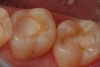

Figure 2  After placement of the glass-ionomer cement, it is allowed to set. Then the "ideal" cavity preparation is made leaving the glass-ionomer cement as a replacement for the dentin in the deep excavated areas of the preparation.

Figure 2

Figure 3  An occlusal view of the completed "closed sandwich" glass-ionomer cement/direct composite posterior restorations.

Figure 3